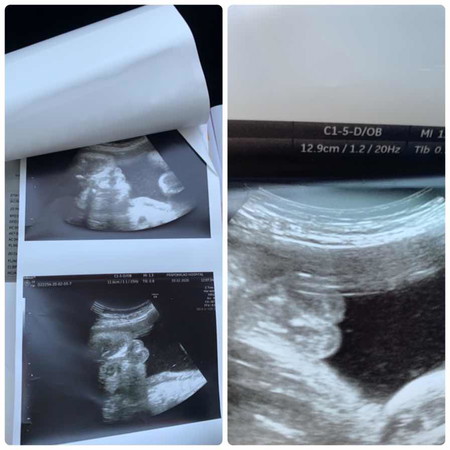

แม่ๆทราบไหมคะว่าเพศอะไร

รูปแรกหมอบอกว่าเพศชายเพราะเห็นเหมือนไข่ รูปที่สองบอกเพศหญิง จะคลอดแล้วยังไม่รู้เพศลูกเลยค่ะ

แม่ว่าชายค่ะ ตอนแรก มองแว๊บแรก คิดว่าหญิงค่ะ เป็นกลีบ ดูอีกที เหมือนผู้ชายค่ะ กลีบน้องไม่น่าจะใหญ่ขนาดนั้นแม่ว่า 😅 เหมือนเป็นไข่มากกว่า 🤭😂☺ รอลุ้นจ้าแม่ จะ ญ หรือ ช น๊าา ถ้าหญิงนี้ โอ้โห้ ใหญ่มากลูกกก 😅😂

พี่สาวเราก็คล้ายๆแบบนี้ หมอบอกผู้ชายไข่ใหญ่ ปรากฏว่าคลอดออกมาได้ผู้หญิงค่ะ ที่เห็นเป็นไข่คือแคมน้อง 😁

น่าจะหญิงนะคะเป็นกลีบๆ เหมือนที่คุณหมอซาวด์ลูกของเราเลยก็เป็นผู้หญิงเหมือนกัน

ส่วนตัวคิดว่าน่าจะเป็นหญิงค่ะ...เพราะถ้าร่องไข่คงไม่ลึกขนาดนั้น

น่าจะชายนะคะ ถ้าหญิงจะเป็นกลีบและร่องชัดเจนแบบลูกสาวเราค่ะ